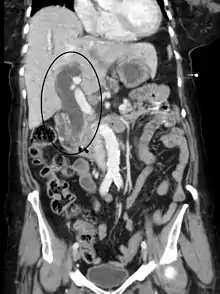

Biliary-tract dilation due to obstruction as seen on CT scan (sagittal plane)

Most people presenting with jaundice have various predictable patterns of liver panel abnormalities, though significant variation does exist. The typical liver panel includes blood levels of enzymes found primarily from the liver, such as the aminotransferases (ALT, AST), and alkaline phosphatase (ALP); bilirubin (which causes the jaundice); and protein levels, specifically, total protein and albumin. Other primary lab tests for liver function include gamma glutamyl transpeptidase (GGT) and prothrombin time (PT).[28] No single test can differentiate between various classifications of jaundice. A combination of liver function tests and other physical examination findings is essential to arrive at a diagnosis.[29]

Medical imaging such as ultrasound, CT scan, and HIDA scan are useful for detecting bile-duct blockage.[32]